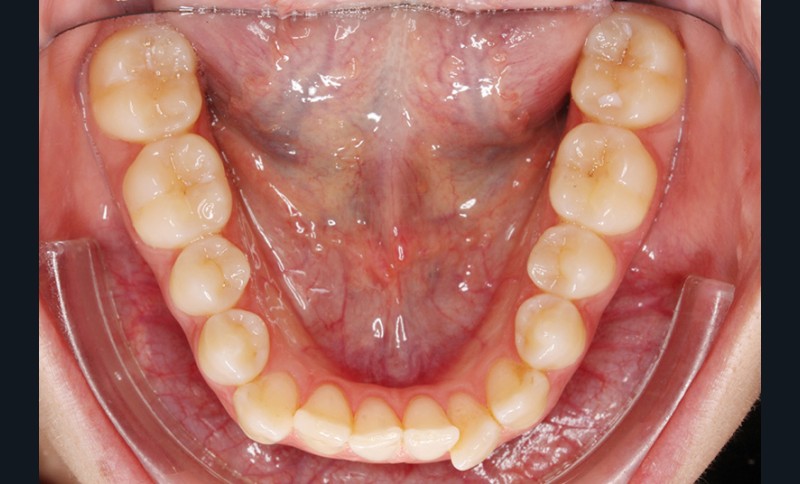

Elle présente une classe I dentaire en denture adulte. Son sourire est perturbé, notamment par la microdontie de son incisive latérale maxillaire droite (la 12). On constate un encombrement modéré au maxillaire (bimarginotopie mésio-palatine et disto-vestibulaire de 13) et plus marqué à la mandibule (monomarginotopie mésio-vestibulaire de 32 et de 43) (fig. 1-6).

À la mandibule, l’encombrement sera résolu par :

– la légère expansion réalisée aux deux arcades suite à la modification des torques latéraux et incisifs en particulier [2] ;

– le stripping incisivo-canin mandibulaire.